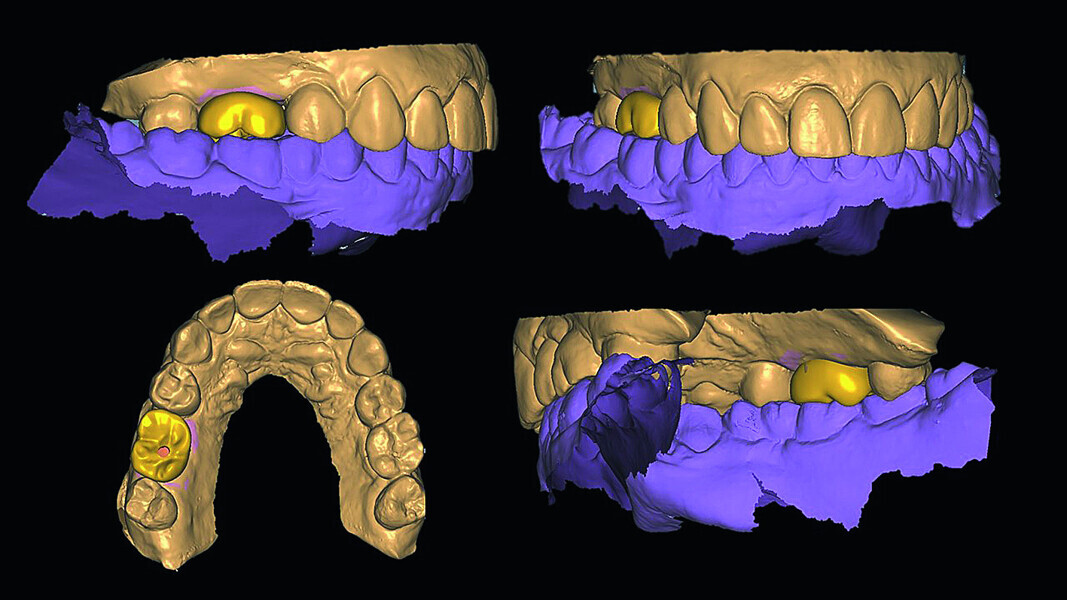

Digital workflow and application of PRF and ozone therapy in oral rehabilitation